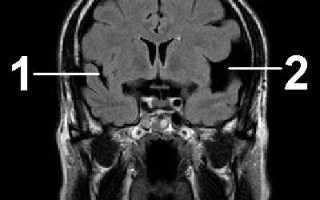

Диагностика заключается в проведении КТ или МРТ.

По результатам этих исследований можно точно установить наличие кисты, ее размеры и местоположение.

Арахноидальная киста головного мозга. Заполненное цереброспинальной жидкостью образование, располагающееся между дупликатурой арахноидальной оболочки. Может иметь врожденную и вторичную природу. Зачастую протекает латентно, без клинических проявлений. При увеличении объема киста дебютирует симптомами внутричерепной гипертензии, судорожными пароксизмами и очаговым неврологическим дефицитом. Диагностируется в основном по данным МРТ головного мозга. При нарастании клинических симптомов требуется хирургическое лечение — дренирование кисты, ее фенестрация, иссечение или шунтирование.

Клиника арахноидальной кисты не имеет специфичных проявлений и соответствует клинической картине, общей для большинства объемных образований головного мозга. К последним относятся внутримозговые и оболочечные гематомы, первичные и метастатические опухоли мозга, абсцесс головного мозга, внутримозговая киста. Осмотр невролога и первичное неврологическое обследование (электроэнцефалография, реоэнцефалография и эхо-энцефалография) позволяют установить наличие интракраниального образования с внутричерепной гипертензией и существующую судорожную активность головного мозга. Для уточнения характера объемного образования и его локализации необходимо проведение МРТ, СКТ головного мозга или КТ.

Оптимальным диагностическим методом для распознавания арахноидальных кист выступает МРТ головного мозга с контрастированием. Использование контрастных веществ позволяет отдифференцировать кисту от опухоли головного мозга. Основным критерием арахноидальной кисты, отличающим ее от опухоли, является отсутствие способности накапливать контраст. При помощи МРТ проводится дифференциальная диагностика с субдуральной гематомой, субарахноидальным кровоизлиянием, субдуральной гигромой, абсцессом, инсультом, энцефалитом и тд церебральными заболеваниями.